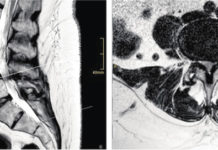

Mal di schiena e sciatica negli anziani: cause, sintomi e terapie

Dolore cronico nel basso della schiena, dolore cronico e formicolio alle gambe: in alcuni casi, questi sintomi possono derivare da un restringimento del canale...